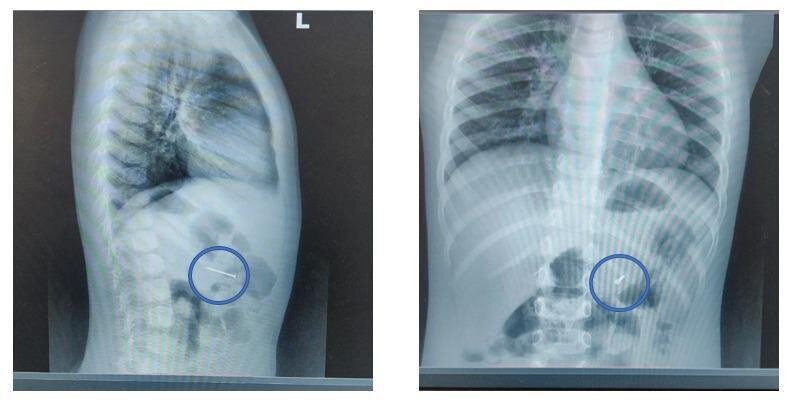

Мальчика экстренно доставили в Детский клинический центр им. Л. М. Рошаля, где врачи на рентгене определили инородное тело в желудке. Гвоздь представляет большую опасность, ведь острым концом он может проткнуть стенки желудка или пищевода, что может привести к перитониту, отметил врач-эндоскопист Руслан Мусаев.

Специалисты с помощью специальных щипцов аккуратно извлекли гвоздь без единого разреза за 20 минут. Сейчас с мальчиком всё хорошо, он был выписан домой в тот же вечер, заверяют в Минздраве.